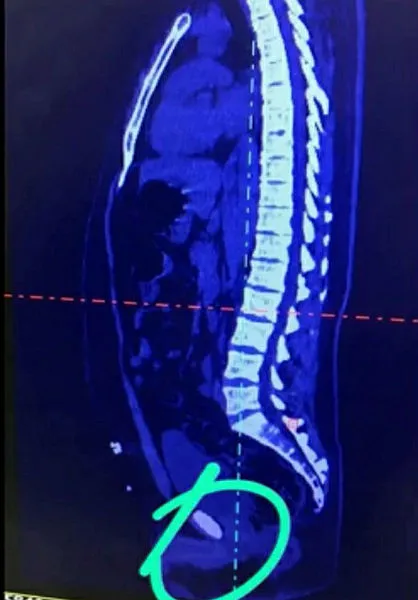

stanbul Havalimanı'nda düzenlenen operasyonlarda, İran'dan yurda sindirim sisteminde uyuşturucu madde taşıyan 5 uyuşturucu kuryesi yakalandı. İl Emniyet Müdürlüğü Narkotik Suçlarla Mücadele Şube Müdürlüğü ekipleri, uyuşturucu ile mücadele kapsamında 15 Ocak ile 3 Şubat tarihlerini kapsayan sürede İstanbul Havalimanı'nda 4 farklı operasyona imza attı. Dış hatlar yolcu terminalinde İran uyruklu kuryeleri yakın takibe alan polis, "yutma" yöntemiyle sindirim sisteminde uyuşturucu madde taşıyan yabancı uyruklu şüphelileri adım adım izledi. Cihazlarda yoğunluk tespit edilmesi üzerine zanlılar muayene edilmek üzere hastanelere götürüldü. Yapılan tetkikler ve röntgen kontrollerinde söz konusu İranlı yolcuların midelerinden 284 kapsül şeklinde 3 kilo 350 gram gelen eroin maddesi ve 8 kapsül halinde 122 gram Afyon Sakızı ele geçirdi. Yakalanan İran uyruklu 5 kurye, emniyetteki ifade işlemlerinin ardından sevk edildikleri adli makamlarca tutuklandı.

Takip altındaki kuryeler üzerinde yapılan aramalarda herhangi bir suç unsuruna rastlanmadı. Farklı tarihlerde gerçekleştirilen operasyonlarda, zanlıların uyuşturucu maddeleri yutarak Türkiye'ye soktukları anlaşıldı. Türkiye'de ilk kez İstanbul Havalimanı'nda kullanılan "yutucu tespit cihazı" ile kontrol edilen şüphelilerin midelerinde uyuşturucu madde yoğunluğu tespit edildi.